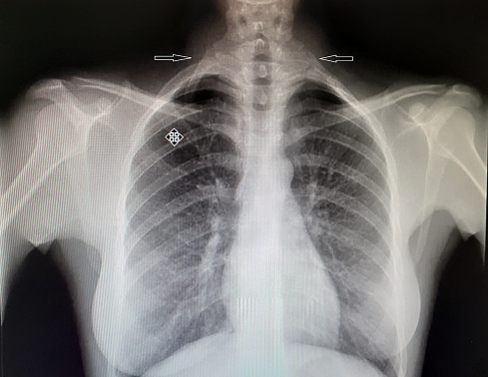

Posteriormente, llegada la cita, el Servicio de Radiología realiza un ecodoppler de troncos supraórticos y revisa placa de tórax, donde observa costilla cervical bilateral (Figura 3). Al realizar el estudio ecográfico dirigido al hueco supraclavicular izquierdo se identifica una arteria subclavia izquierda posterior a la primera costilla cervical, discretamente más dilatada que la derecha, pero sin imágenes aneurismáticas ni signos de complicaciones vasculares. Se trata de una variante anatómica sin significación clínica en la actualidad, pero de la que conviene conocer su existencia ya que a lo largo del tiempo podría presentar sintomatología asociada al síndrome del desfiladero torácico por compresión del plexo braquial, vena o arteria subclavias.

Además, se continúa estudio con radiografía de tórax, en la que se observa un pulmón sin cambios agudos, y una analítica, con perfil general de reconocimiento, con resultados dentro de la normalidad.